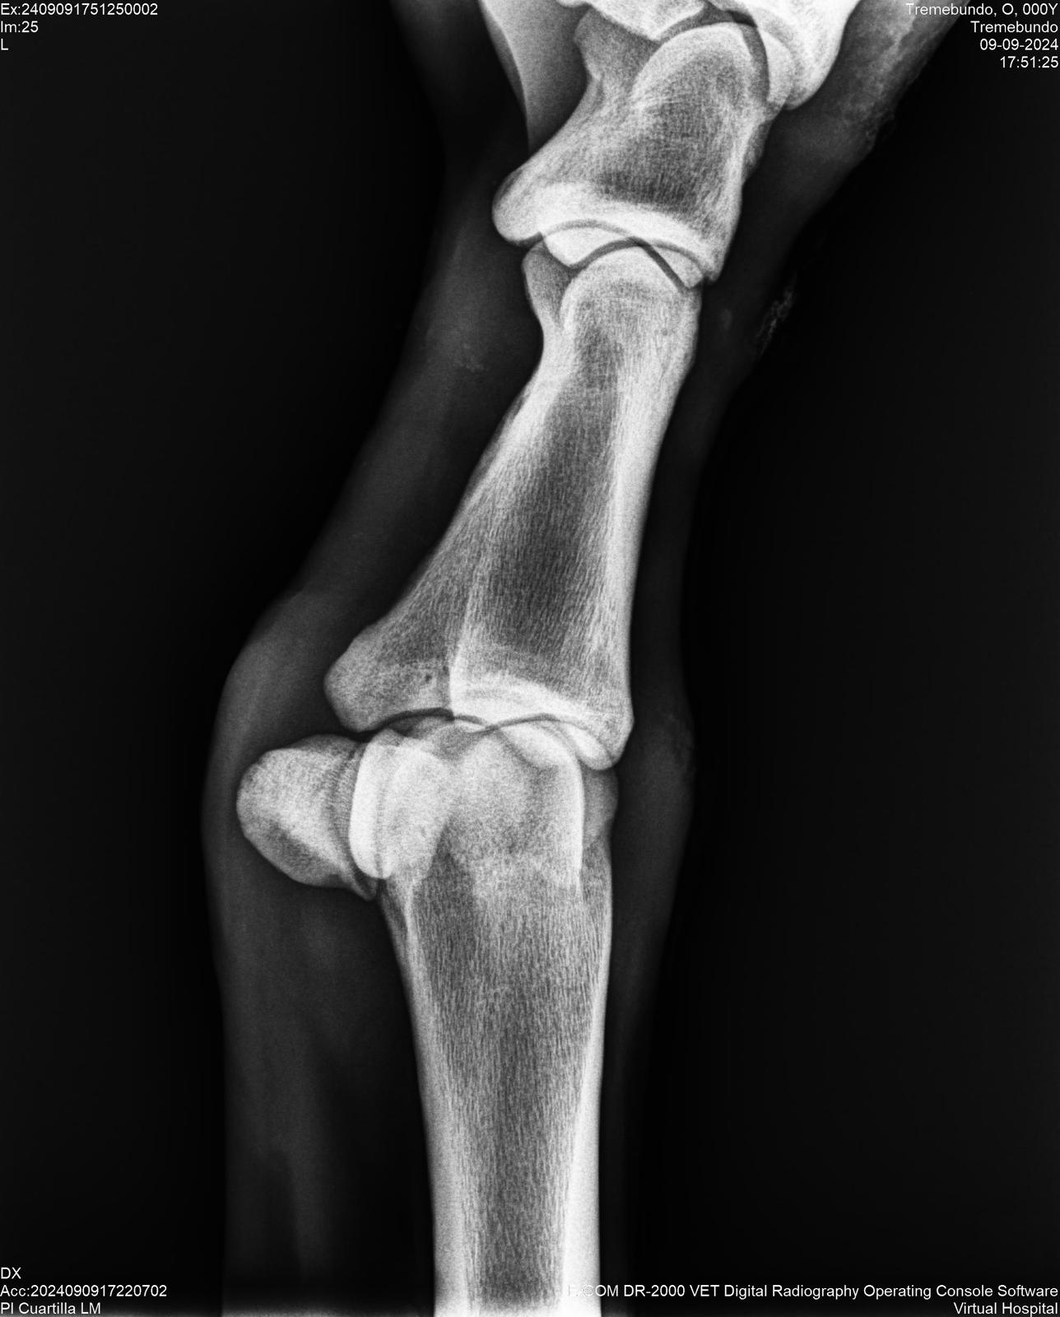

LOTE 37, TREMEBUNDO

Generacion 2022